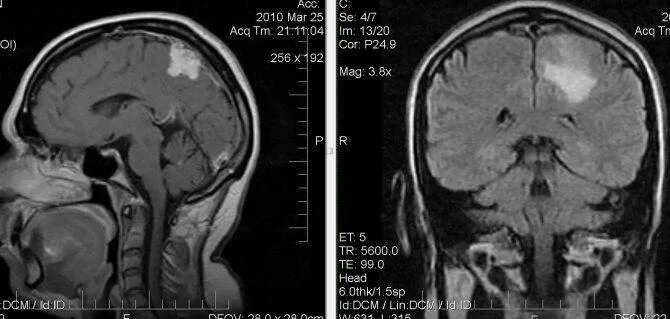

Чем отличается кт от мрт головного